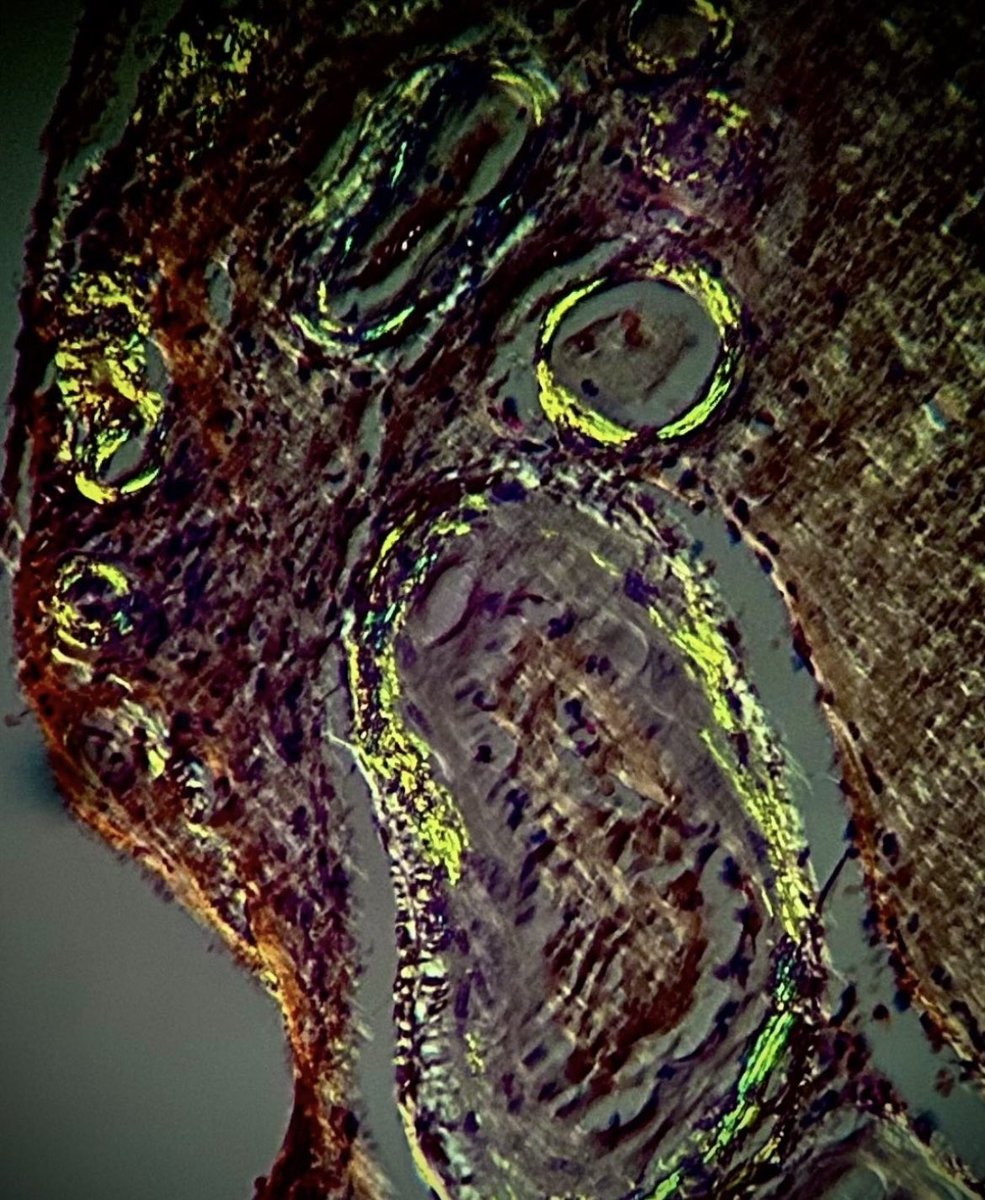

#GUpath external re-review🔬of penile lesion in a patient with a h/o penile cancer at this site (s/p partial resection a year back) recurrent cancer? dysplasia? negative for malignancy? #pathresidents: what say you?🤔

slusagar's tweet image. #GUpath external re-review🔬of penile lesion in a patient with a h/o penile cancer at this site (s/p partial resection a year back)

recurrent cancer?  dysplasia? negative for malignancy?

#pathresidents:  what say you?🤔